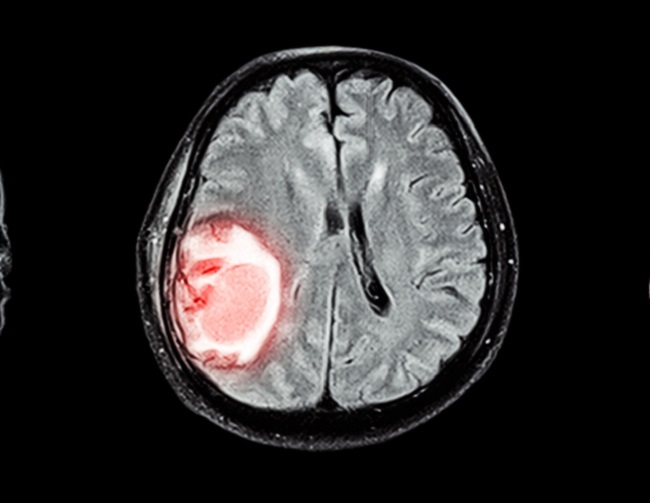

Selama ini, terdapat dogma yang menganggap bahwa penurunan tekanan darah pada fase akut stroke hemoragik dapat menyebabkan perburukan iskemia pada area perihematoma. Tekanan darah sangat sering meningkat pada kasus stroke hemoragik akut. Hal ini diduga disebabkan adanya peningkatan tekanan intraserebral, hipoksia, nyeri, stress akibat stroke, serta riwayat hipertensi sebelumnya.[1,2]

Selama ini, penurunan tekanan darah pada fase akut stroke hemoragik merupakan topik yang kontroversial. Ada studi yang mengatakan bahwa penurunan tekanan darah berkaitan dengan iskemia perihematoma, tetapi ada pula studi yang menyatakan sebaliknya.

Penurunan tekanan darah pada fase akut stroke hemoragik adalah sesuatu yang kontroversial. Beberapa studi menyatakan bahwa penurunan tekanan darah dapat menyebabkan iskemia di area perihematoma akibat penurunan perfusi darah serebral, tetapi studi lainnya menunjukkan bahwa kedua hal ini tidak berkaitan.